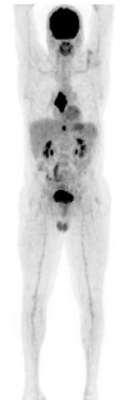

Axumin pet scan for prostate cancer. Axumin is an fda approved medicare covered scan that can achieve early detection of recurrent prostate cancer after surgery or radiation. It is the first fda approved f 18 labeled pet scan agent indicated in patients with suspected recurrent prostate. Axumin is a novel molecular imaging agent indicated for use in pet imaging to identify suspected sites of prostate cancer recurrence in men who have elevated blood levels of prostate specific antigen psa following prior treatment. For years we have been able to detect prostate cancer recurrences with psa but standard body and bone scans have been unable to determine the location of the cancer until the psa level is excessively elevated 10 to 30 or higher.

For years we have been able to detect prostate cancer recurrences with psa but standard body and bone scans have been unable to determine the location of the cancer until the psa level is excessively elevated 10 to 30 or higher. Axumin a 18 f fluciclovine injection is a molecular agent used in positron emission tomography pet imaging in men with suspected recurrent prostate cancer. Axumin based pet ct scans and detection of recurrent prostate cancer posted on april 30 2020 by sitemaster a new report from a relatively small single institution study has provided additional information about the utility of 18 f fluciclovine axumin pet ct scans in the detection of recurrent prostate cancer after definitive first line treatment. Axumin pet showed mild activity suvmax 1 5 in the prostate bed but not significantly higher than the blood pool activity suvmax 1 4 thus not suspicious for recurrence at the prostatic bed per the guideline.

Axumin is indicated for positron emission tomography pet imaging in men with suspected prostate cancer recurrence based on elevated psa levels following prior treatment. Axumin is an fda approved medicare covered scan that can achieve early detection of recurrent prostate cancer after surgery or radiation. Conventional ct and nuclear medicine bone scans have limited sensitivity especially in patients with low psa levels less than 10 ng ml. Thereafter the patient was referred to our center for axumin pet scan.